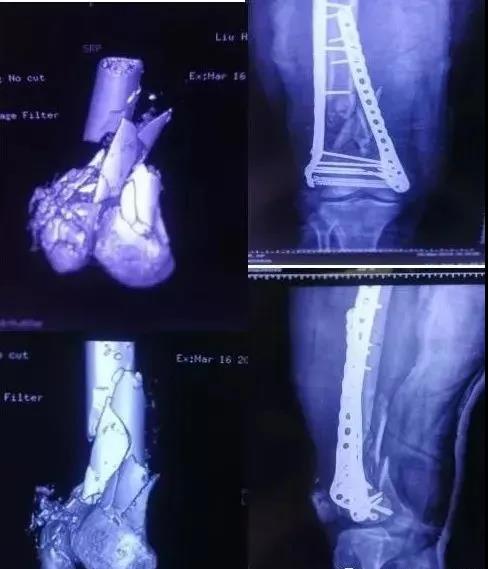

7)胫骨远端(pilon,踝部)

- pilon骨折,高能损伤,6-8h肿胀未形成,可以急诊做,手术时间<3小时。

- 10-14天,分步延期手术策略。

- 踝部骨折手术时机同样取决于皮肤条件。